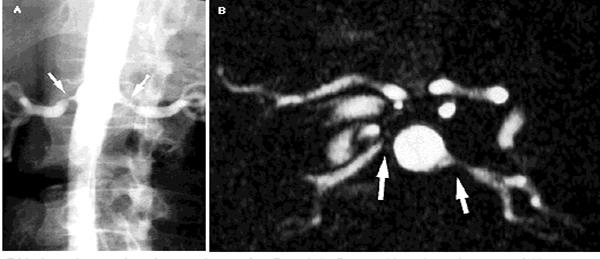

Рисунок 10.Магнитно-ядерный резонанс.

Двусторонний стеноз почечных артерий. А: стандартная ангиограмма аорты выявила двусторонний стеноз у устья правой и левой почечной артерии (стрелки).

Б: стандартная ЯМР-ангиограмма на том же уровне обнаружила те же изменения (стрелки). (Рисунки Jonathan Kruskal, MD, PhD.)